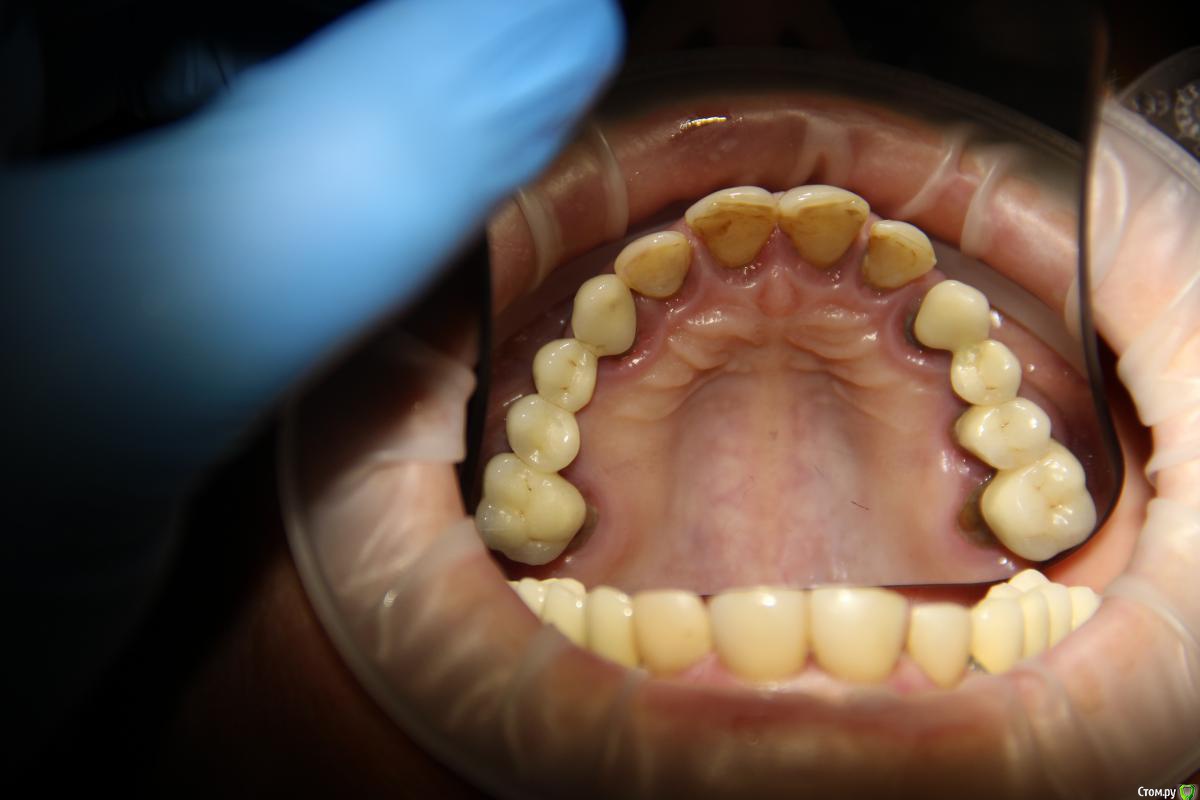

Популярный пост Abuk Опубликовано 24 ноября, 2015 Популярный пост Поделиться Опубликовано 24 ноября, 2015 Планировали 8 имплантатов.Буду рад конструктивной критике.Фото с мокап.Через 6 днейДалее хотели поставить 6 ки, она отказалась (не хотели синусы)и решили все по-другому .Через 2мес пришла с отколотыми консолями )Прошу прощения ,что ортопедию выложил не в том разделе), не хотел делить. 26 1 Ссылка на комментарий

Abuk Опубликовано 24 ноября, 2015 Автор Поделиться Опубликовано 24 ноября, 2015 (изменено) Радикально Вы. Что оставили ей после имплантации-это инд аббатменты? На них мокап одели и нагрузили сразу? У всех был торк хороший? Или это временные абб? Что за систему использовали? В планах консоль назад, правильно я понимаю?Спасибо.увидев такую работу,сам так же подумал бы). Но там подвижность 2-3 ст. ближе к 3. Мосты болтались ,2 ки в хлам. 1 ки только стабильны. Снимал мосты,проводил кюретаж. Решил дернуть.Абатманы временные, тех. сделал на них коронки. Система анкилоз. Работа,на посл. фото, постоянная . Имплы в области 4 и по одному моляру ,консоли. Мок ап был до имплантации . По нему шаблон. Стабильность 15 -20 на 23 , остальное больше 30. Изменено 24 ноября, 2015 пользователем Abuk 1 Ссылка на комментарий